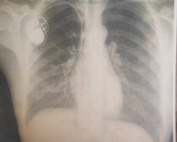

د.أبو سلمية: تدهور الوضع الصحي لمرضى الكلى في مجمع الشفاء الطبي

في يوم الصحة العالمي .. قطاع غزة بلا دواء واوضاع كارثية